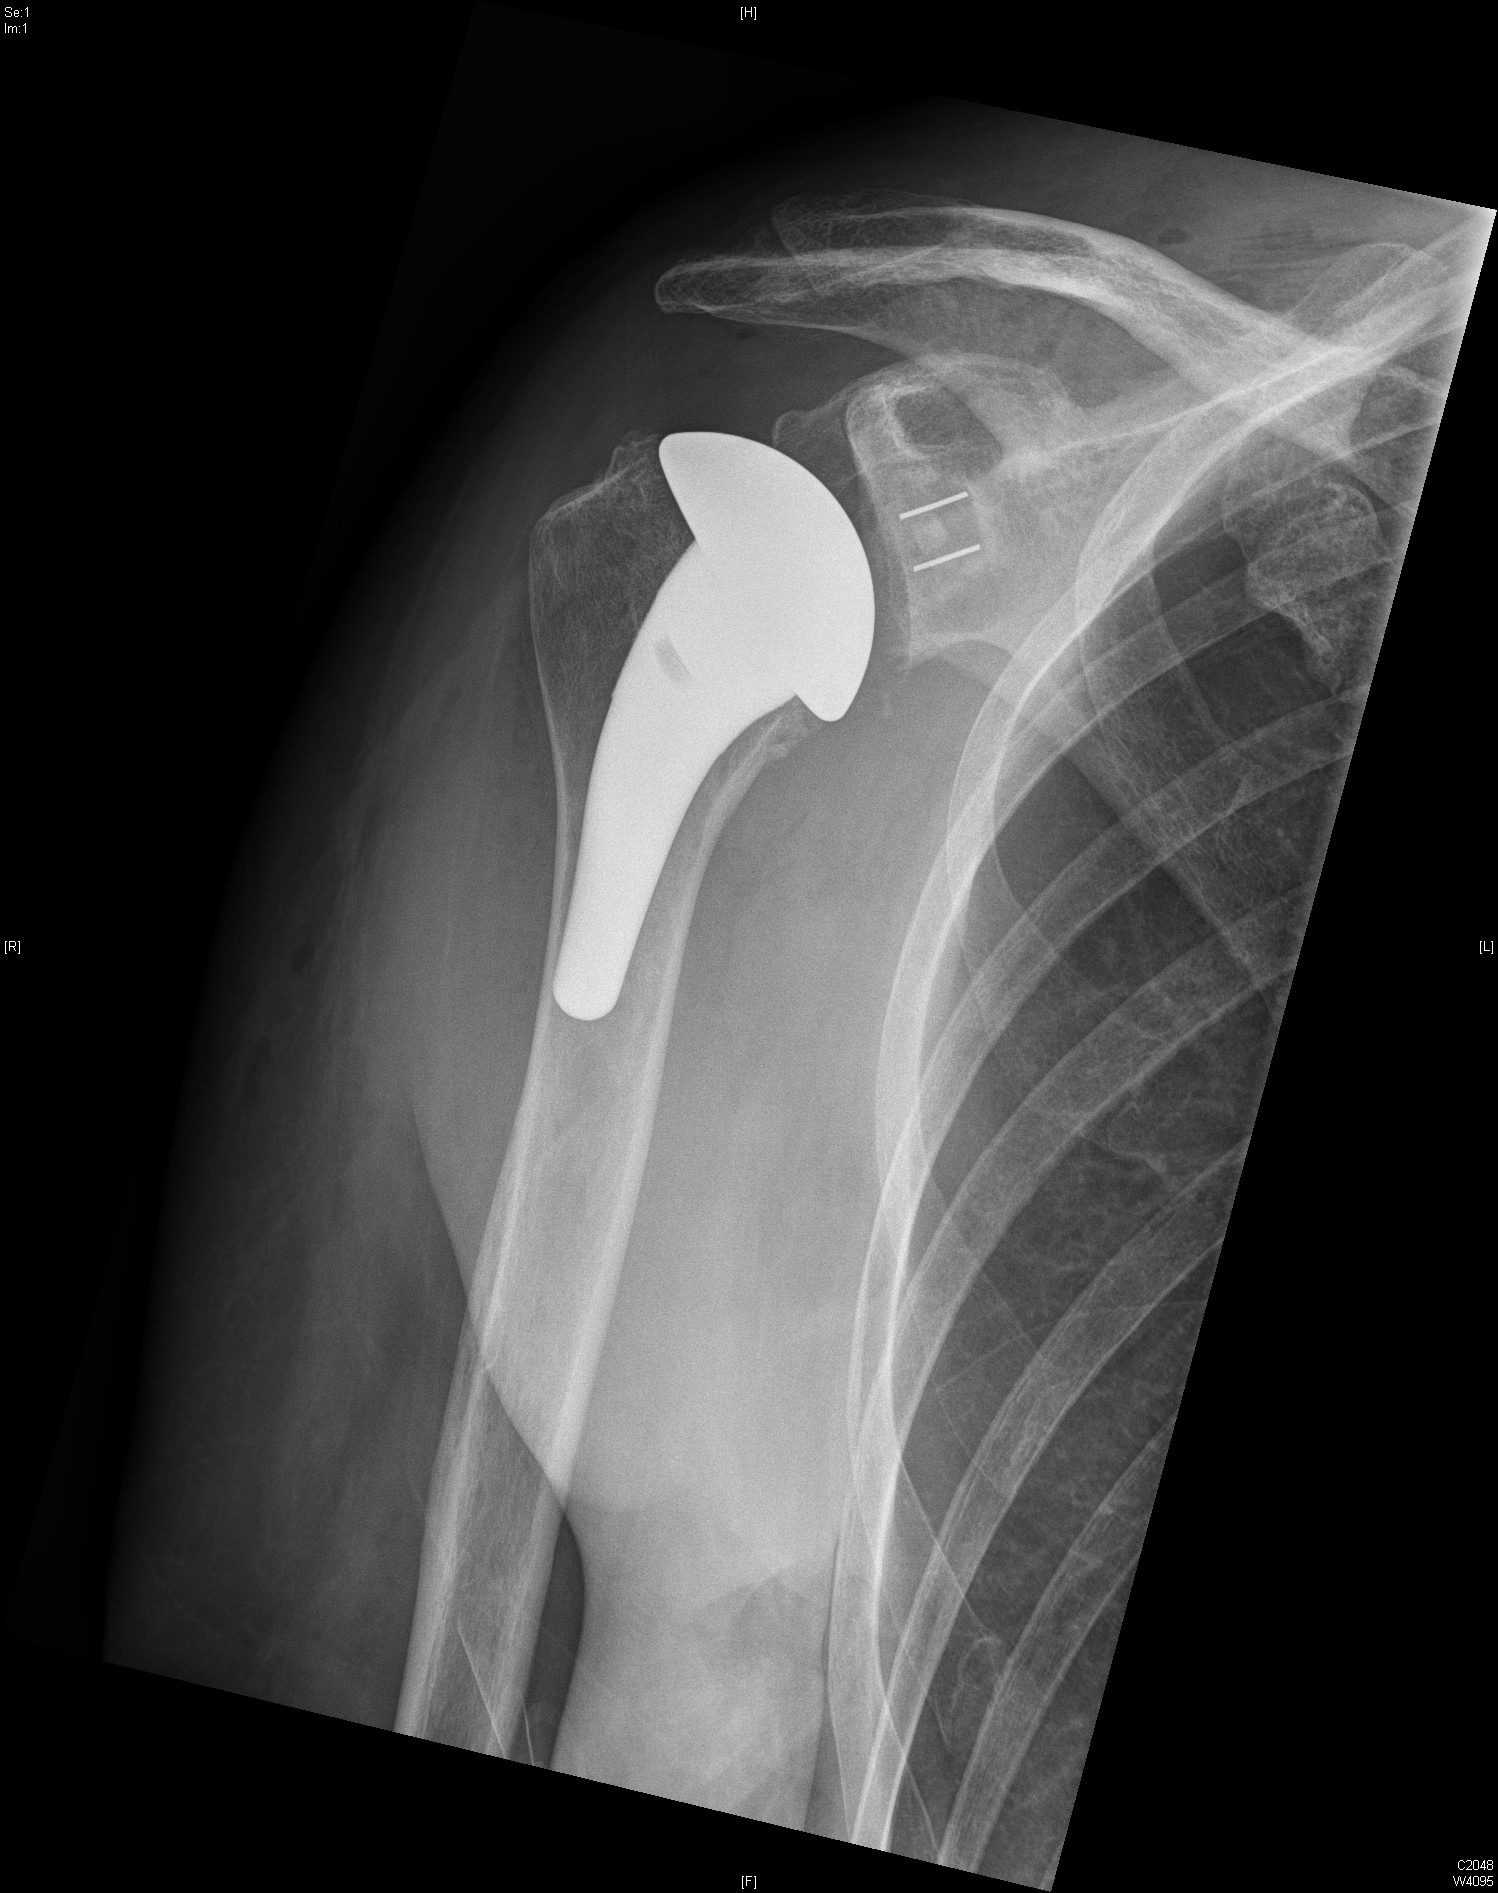

Anatomische Schulterprothese